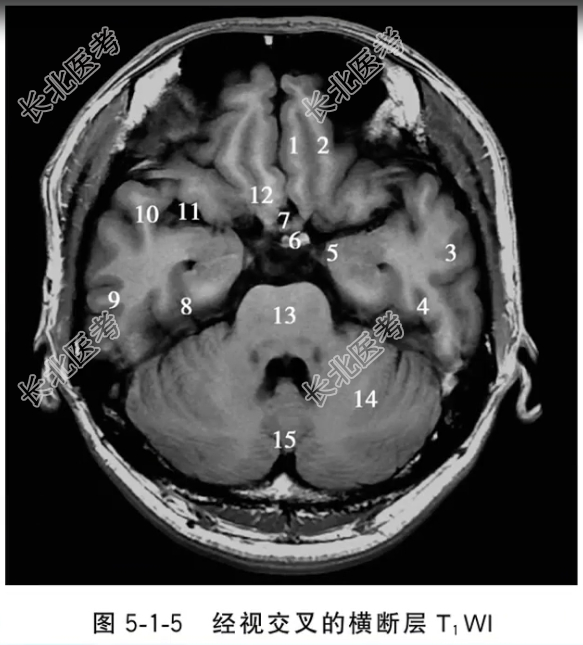

- 单项选择题经视交叉的横断层T1WI中,标记为7的结构是

A、直回

B、视交叉

C、漏斗

D、脑桥

E、外侧沟